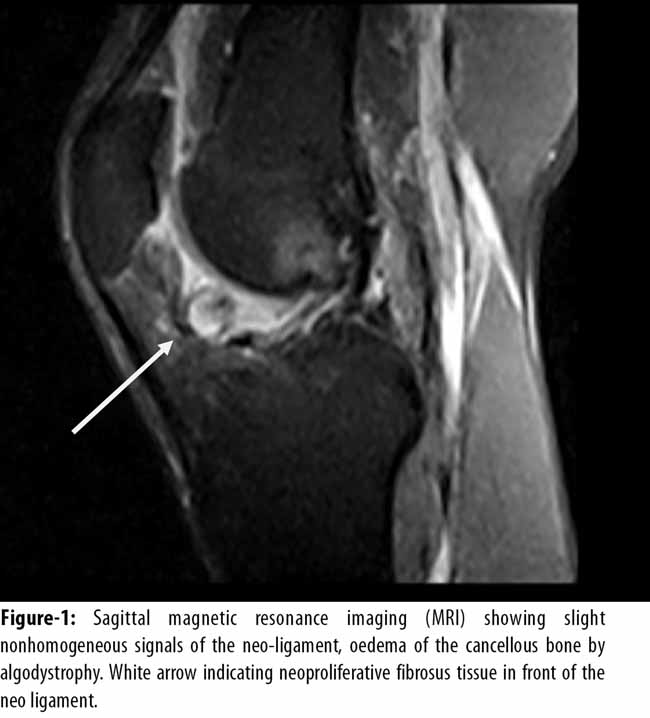

At physical examination, there was no swelling or effusion of the knee. The stability test of knee (Lachman test, Jerk, Pivot Shift, drawer front) were unremarkable and no signs of meniscal tear or cartilage pathology were found. The extension deficit was 7 degrees with pain at terminal extension and deficit of hyperextension. Knee flexion was complete. Magnetic resonance imaging (MRI) was performed which showed slight non-homogeneous signals of the neo-ligament, hyper-intense signals at the external femoral condyle, oedema of the cancellous bone by algodystrophy, degenerative phenomena of both meniscus. Sagittal sections were very suggestive of Cyclops syndrome, with neoproliferative fibrous nodule in front of the neo ligament, producing impingement of the inter-condylar notch (Figure-1 and 2)